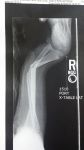

So, I was just minding my own business, not bothering anyone, when this boulder climbing wall comes along and.....you know..... starts making me climb it.  Yada Yada Yada, two plates and 11 screws later, I am laying back in the recliner being thankful it was not worse!

Yes that is the before shot. I have not seen it since the surgery, so I am looking forward to that! Just trying not to overdo the Oxycontin and checking back here for inspiration.

You nailed it.  I was watching the "whippersnappers" going up the cliff, and my 13 year old wanted to try it but he was shy.  I really did not see the big deal, because the handholds were man made and the base had shredded tires.  So as I started up, my kid was watching, so the crowd started yelling which handhold. I figured my kid would not be shy about it once I was done.  I kept going up and with each handhold, the crowd was shouting more, so the next thing I knew I was at the ledge and the guys yelled "pull up!" so I did a pull up and they went more over the top.  When I dismounted, the drop was not that bad, BUT THE DAMN SHREDDED TIRES HAD A BIG DIVIT right where I landed and caught me more than "foot deep" so instead of a flat footed drop, my left fibia and tibia took (at least half) of my 180 pounds.  Snap.  The whole crowd heard it and the guys cheering me on ran for the hills! I really am taking something away from this one.  There was no reason for me to do that.  I was showing off.  There was no need to take the risk, and frankly, I am glad my kid did not break his foot.

I can't look at your foot and ankle for long ... it makes me queasy ... it looks soooo damn painful ... unh ...